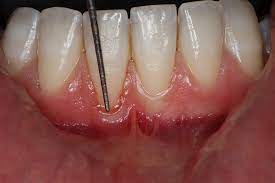

Periodontics is a specialized branch of dentistry that focuses on the prevention, diagnosis, and treatment of diseases affecting the supporting structures of the teeth primarily the gums (gingiva), alveolar bone, cementum, and periodontal ligament. These tissues together form the periodontium, which anchors and supports the teeth in the jaw.